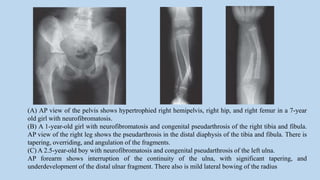

(A) AP view of the pelvis shows hypertrophied right hemipelvis, right hip, and right femur in a 7-year

old girl with neurofibromatosis.

(B) A 1-year-old girl with neurofibromatosis and congenital pseudarthrosis of the right tibia and fibula.

AP view of the right leg shows the pseudarthrosis in the distal diaphysis of the tibia and fibula. There is

tapering, overriding, and angulation of the fragments.

(C) A 2.5-year-old boy with neurofibromatosis and congenital pseudarthrosis of the left ulna.

AP forearm shows interruption of the continuity of the ulna, with significant tapering, and

underdevelopment of the distal ulnar fragment. There also is mild lateral bowing of the radius